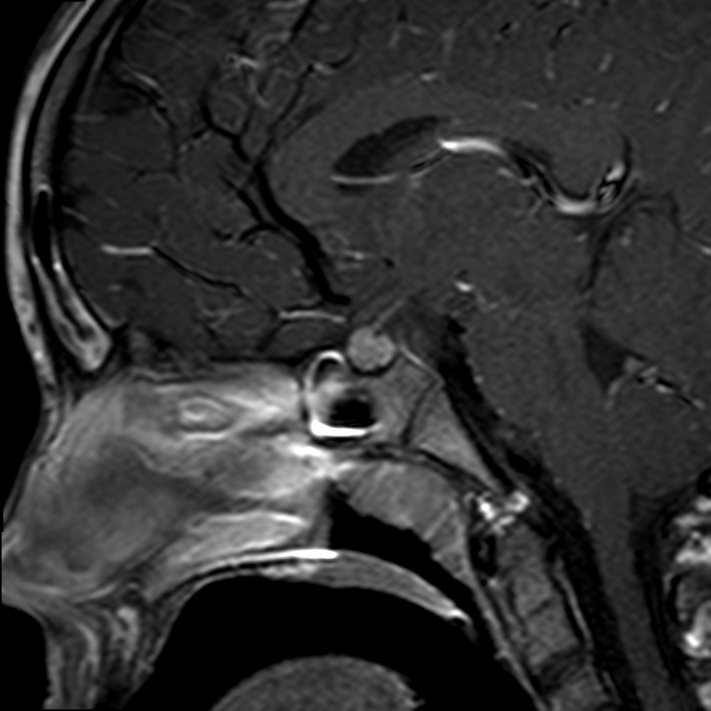

Caso neurorradiología

Paciente de 60 años con cuadro de 1 semana de evolución consistente en tropiezos frecuentes y alteración en la movilidad del miembro

inferior derecho. No refiere

cefalea u otros síntomas asociados, no pérdida de peso, no náuseas o emesis, no

sudoración nocturna. Antecedentes de hipertensión arterial y diabetes.

Resonancia magnética